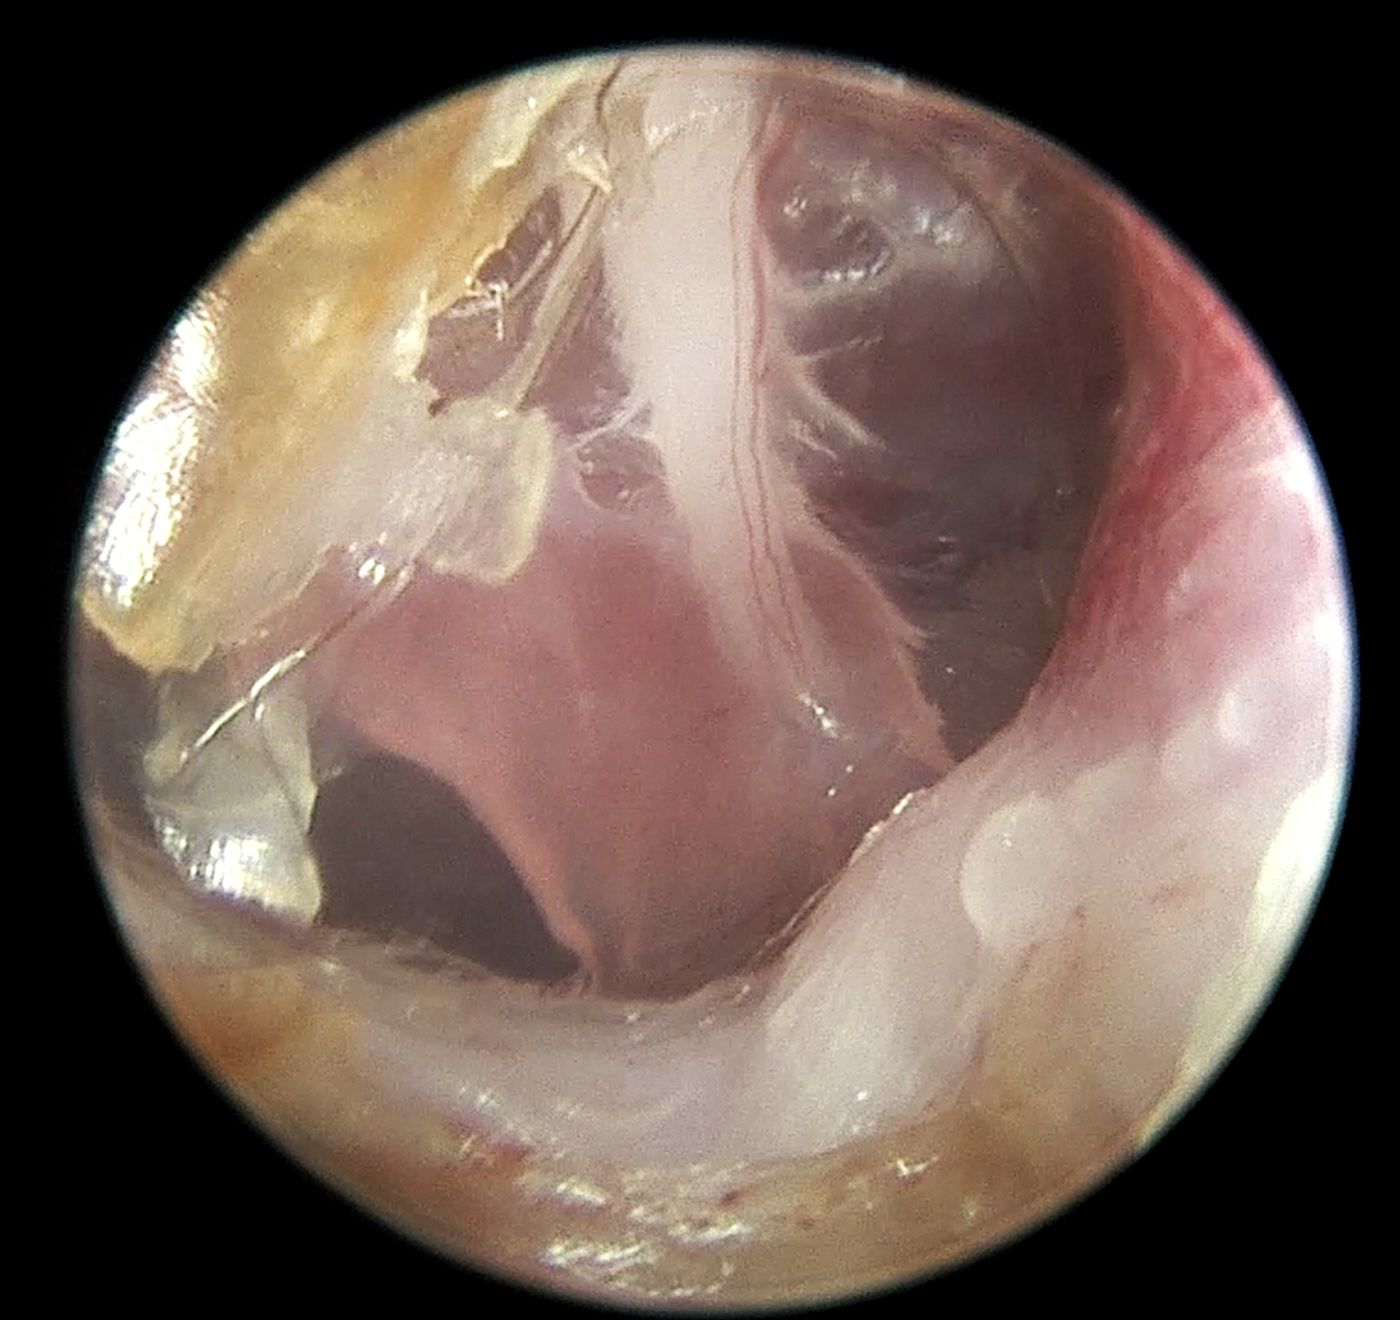

Diagnostyka endoskopowa zewnętrznych przewodów słuchowych (Otoendoskopia)

Głębokie płukanie przewodów słuchowych w znieczuleniu ogólnym

Myringotomia (nakłucie błony bębenkowej z oczyszczeniem z wydzieliny zapalnej) w celu diagnostyki i leczenia zapalenia ucha środkowego i wewnętrznego

Usuwanie ciał obcych (kłosy, bezoary)

Pobieranie biopsji tkanek zmienionych

Resekcję zmian nowotworowych w obrębie ucha zewnętrznego, także przy użyciu lasera